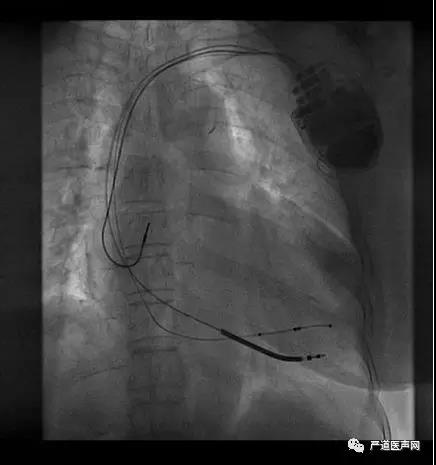

病例八

术前冠脉造影

血管选择 一

血管选择二

血管选择三

术中测试

● 左心室阈值:LV4-Coil 1.25V

● 右心室阈值:0.5V

● 右心房阈值:0.5V

最终影像